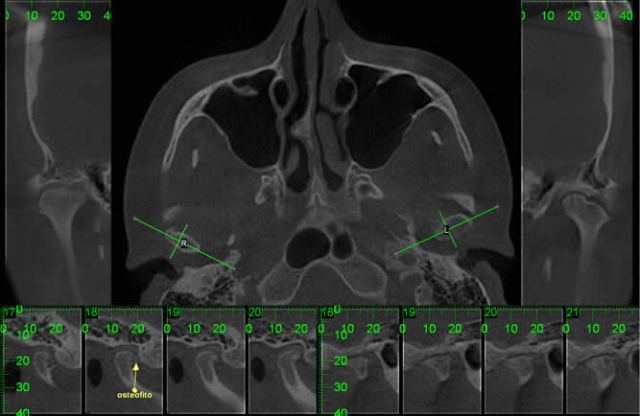

* ATM

Visualização dos componentes ósseos com a maior resolução existente na atualidade.

CASO 1 - Anquilose de ATM

Paciente com assimetria, limitação de abertura bucal. Observa-se união óssea da porção posterior e lateral do côndilo ao esfeóide e zigomático.